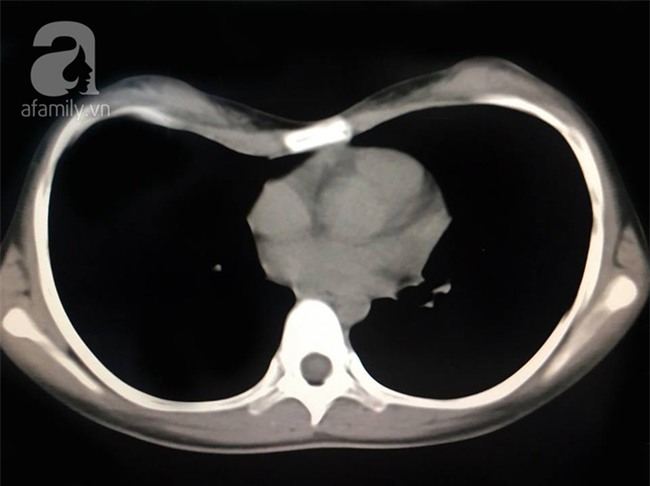

Mãi đến gần đây, em M. mới được người nhà đưa đến khám tại phòng khám chỉnh hình nhi bệnh viện Xuyên Á. Các kết quả lâm sàng và chụp cắt lớp CT cho thấy tình trạng ngực lõm từ nhỏ của bệnh nhi có biểu hiện tăng dần. Đến thời điểm thăm khám tại BV, diện tích ngực lõm đã lên đến 10x20 cm, khiến lồng ngực bị thu hẹp khá sâu, gây nguy cơ chèn ép tim phổi rất cao.

Ảnh chụp phim cho thấy bệnh nhân M. bị lõm ngực nặng.